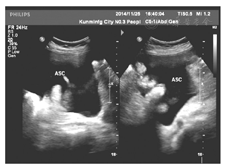

病例2王某,女,71岁,因卵巢癌晚期合并大量腹水于2014年11月25日入院。患者约于1年前被诊断为卵巢癌,行腹腔镜手术(术式不详),经过6次化学药物治疗。于4个月前出现腹腔积液。本次入院主要是因为大量腹水至卧床、呼吸困难,时有腹部疼痛,见图3。入院后的第5日,我们给予腹部穿刺、置入微管持续引流,每日控制引流1 500 ml,引流半月腹水无减少情况,多为渗出性,腹水中有癌细胞检出,患者虚弱。于入院后第20日开始给予三氧水腹腔内灌注引流,每日2次,每次100 ml,灌注后闭管2 h后开放引流。3 d后引流量开始减少,连续7 d后,每日开放引流,24 h腹水量减少至200 ml,渗出液中癌细胞数、红细胞数明显减少。于引流后第9日患者夜间活动时引流管脱落,未再引流。隔日复查B型超声仅为少量腹腔液体,好转出院,见图4、图5。